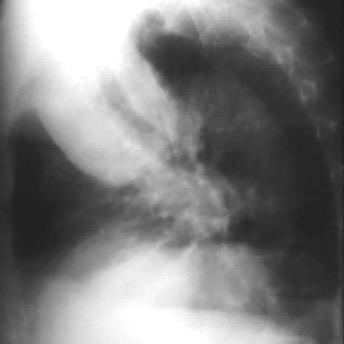

Marzo 2014: Perforación longitudinal distal secundaria a episodio de vómito (síndrome de Boerhaave). Derrame pleural izdo. que evoluciona a empiema.

Wang C-T et al. Tension hydropneumothorax in a Boerhaave syndrome patient: A case report . World J Emerg Med, 2021. Katabathina V et al. Nonvascular, nontraumatic mediastinal emergencies in adults:a comprehensive review of imaging findings. Radiographics. 2011.